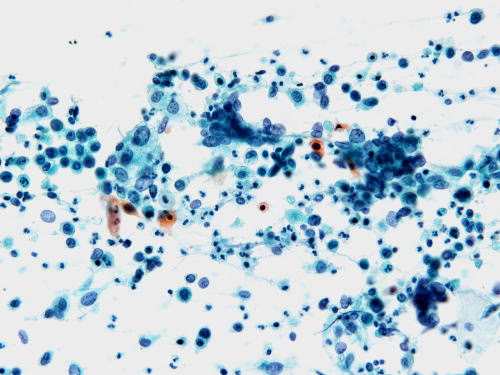

| 採取された材料中の細胞一つ一つを顕微鏡下で観察し、異常細胞の有無を調べる検査です。病気の早期発見や疾患の良性・悪性の推定が可能です。組織検査と比べ、患者さんへの侵襲が少なく再検査をしやすいのが特徴です。 対象となる材料として子宮膣部・頚管および体部内膜の擦過、喀痰、尿、体腔液、病変部からの穿刺吸引などがあります。 |

2 標本の染色![]() パパニコロー 染色標本です |

3 鏡検![]() 標本中の全細胞を観察し 異常細胞の有無を検索します |

![]() 子宮膣部の正常細胞 |

![]() 子宮膣部の癌細胞 |